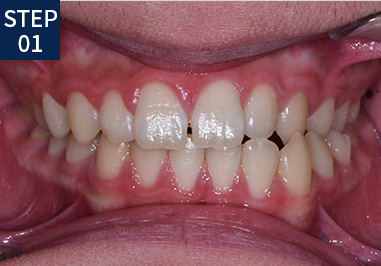

당신만을 위한 치아교정 1:1 프로세스

• 기초 조사 및 상담

• X-RAY/구강/안면촬영

• 치열을 위한 인상채득

• 분석 및 치료계획 수립

• 진단 및 상담

• 장치 장착, 치료